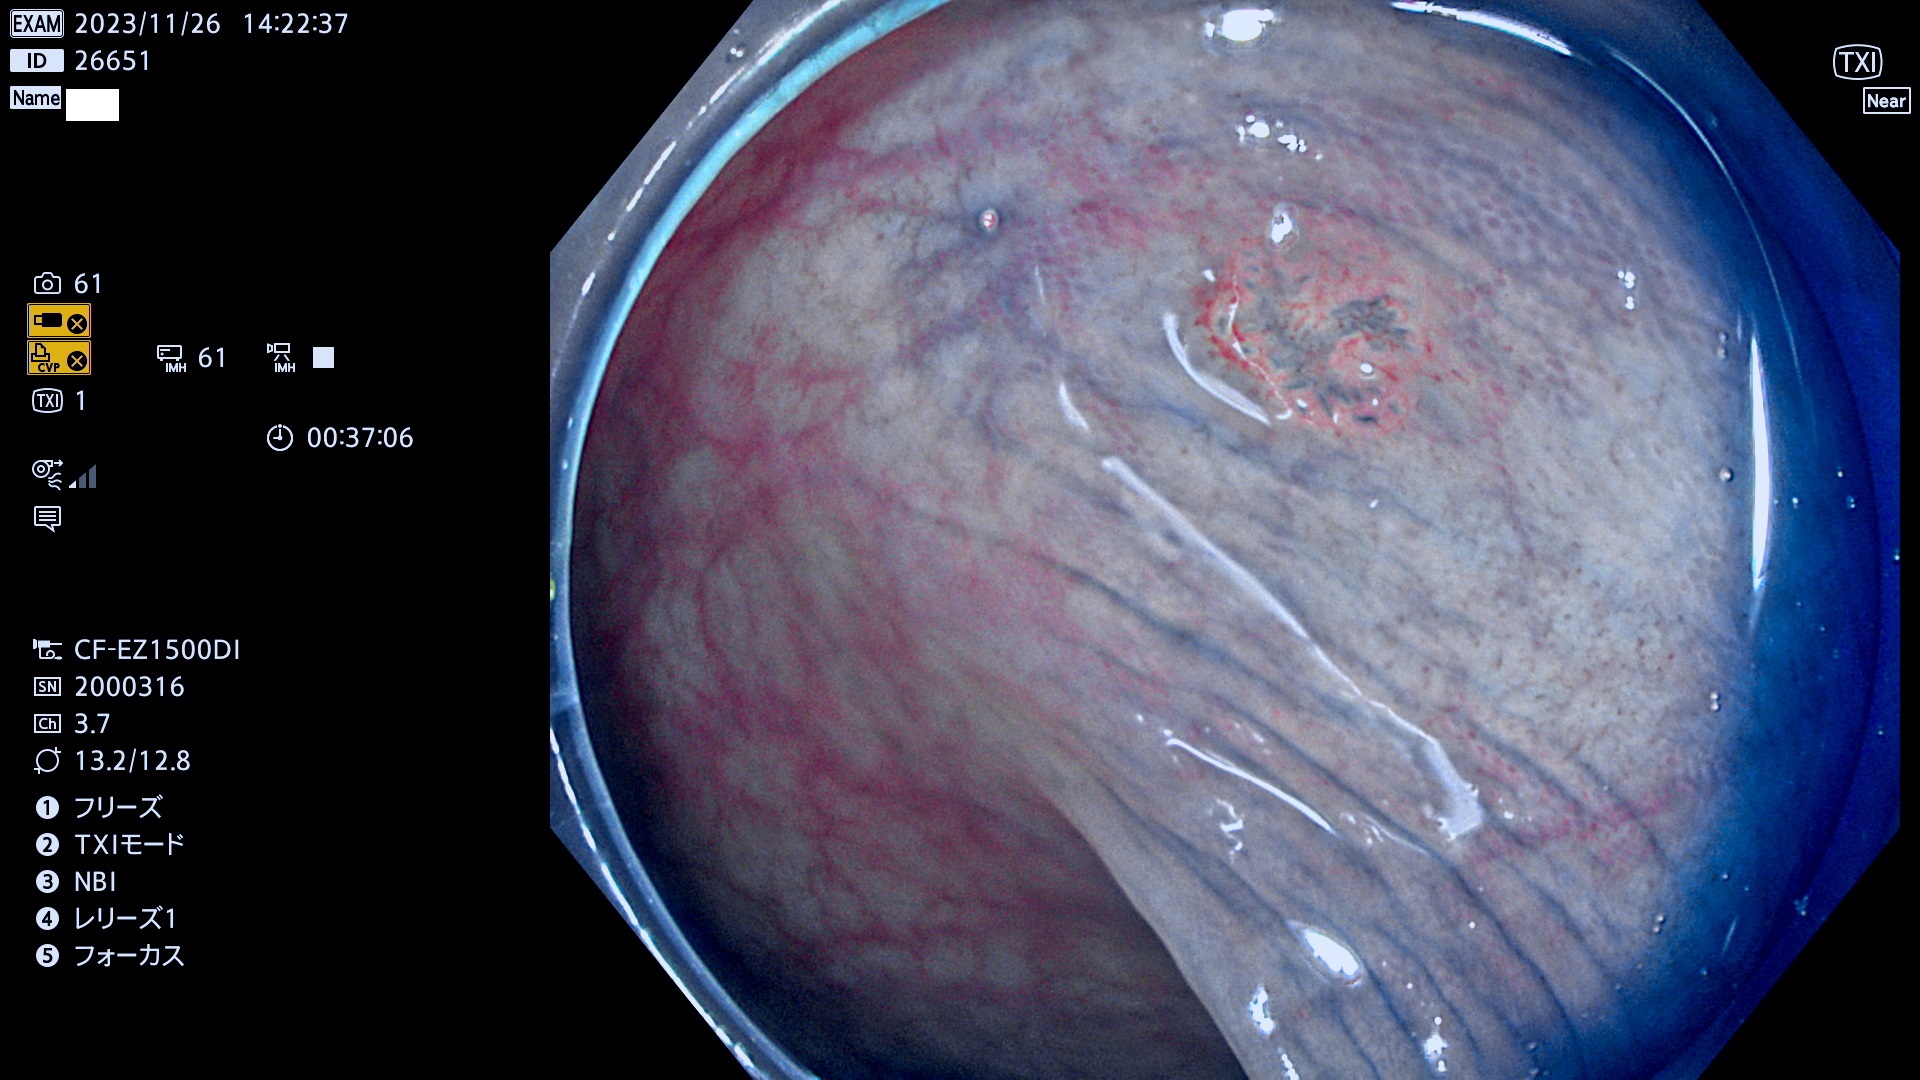

表面型腺腫(Flat Adenoma)の中で、完全に平坦な物をUb、陥凹している物をUcと呼びます。平坦隆起型(Ua)よりも、発見が難しく危険な病変です。このタイプは「内視鏡後・大腸癌の重要犯人」であり、この発見率は「腺腫発見率」よりも、重要な意味があります。

毎週の検査(木・金・土・日)に発見されたUb、Uc型・腺腫を、その週の日曜の夜にUPし1週間、提示します。

抽出の対象期間 2023年11月23日(木)〜11月26(日)の4日間(48件の検査)8件